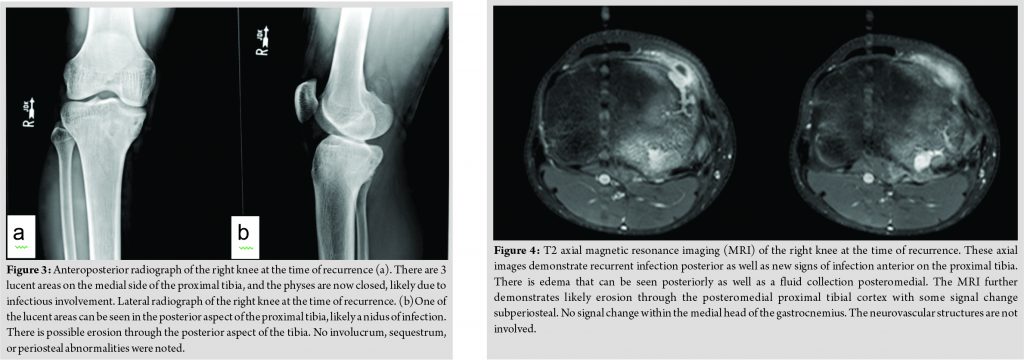

In April of 2017, approximately 1 year after completing therapy, he was seen in the infectious disease clinic again. At that time, the patient reported a 7-day history of pain, redness, and swelling along the inner aspect of the right upper leg below his knee overlying his prior surgical site. However, his father reported that he had complained of these findings for several months. A firm, tender erythematous mass over the medial aspect of the proximal tibia was noted on examination, underlying his surgical scar, although no drainage was present and the range of motion of his knee was normal. He had been a febrile and denied any recent trauma to the area. His ESR and CRP were normal at this time, as was his total leukocyte count and his differential leukocyte count. Plain radiographs demonstrated concern of recrudescent chronic osteomyelitis in the proximal tibia, with worsening sclerotic changes compared with his most recent radiograph (Fig. 3). A contrasted MRI demonstrated abnormal signal intensity in the proximal tibial metaphysis and epiphysis, with an abscess connected to a nidus of presumed chronic osteomyelitis througha fistula tract running inferior to the physis (Fig. 4 and 5). He was taken to the operating room shortly after this, where an abscess eroding through to the posterior aspect of the proximal tibia was noted. The superficial portion of the abscess was drained, with drilling through the affected bone into the posterior aspect of the tibia followed by curettage of the entire area. A cortical window was not created nor was periosteal elevation noted. His post-operative wound healing was uneventful. Operative cultures produced monomicrobial growth of P.aeruginosa, which, given the heavy growth in the primary streaks on the agar plate, was not felt to be a contaminant. This isolate demonstrated intermediate resistance to piperacillin-tazobactam (minimum inhibitory concentration (MIC)=32/4 mg/L), resistance to gentamicin (MIC>2 mg/L), aztreonam (MIC>16 mg/L), and ciprofloxacin (MIC>2 mg/L).The isolate was susceptible to meropenem (MIC of 1 mg/L), cefepime (MIC of 8 mg/L), ceftolozane and tazobactam (MIC=1.5 mg/L), and ceftazidime (MIC of 4 mg/L).Cefepime and ceftazidime MICs were confirmed with E-testing. Noimprovement was seen after 72 h of empiric cefazolin, but he did improve following transition to meropenem. Immunological evaluation revealed normal levels of natural killer cells, immunoglobulins (IgG, IgA, IgM, and IgE), tetanus, and pneumococcal antibodies. A lymphocyte subset panel was normal. He also demonstrated a normal lymphocyte proliferation response to phytohemagglutinin and pokeweed mitogen and a non-reactive serology to human immunodeficiency virus.Given the absence of an oral treatment option, he was treated initially with several days of cefepime, followed by 49 days of meropenem. He was then transitioned back to cefepime for 14 days followed by 56 days of ceftazidime. A contrasted MRI performed 7 weeks and plain radiographs performed 3 months into treatment demonstrated no recrudescence of disease (Fig. 6). He maintained normal inflammatory markers during treatment. At the end of 4 months of therapy, his physical examination was normal and his antibiotic therapy was discontinued. He denied any persistent symptomatology and was participating in soccer again without difficulty.